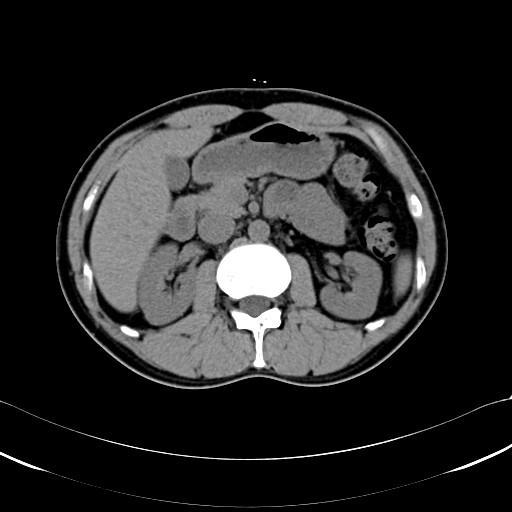

ちなみにこっちは1年半前の2010/5/27です。

腹回りの脂肪に著変なしw。